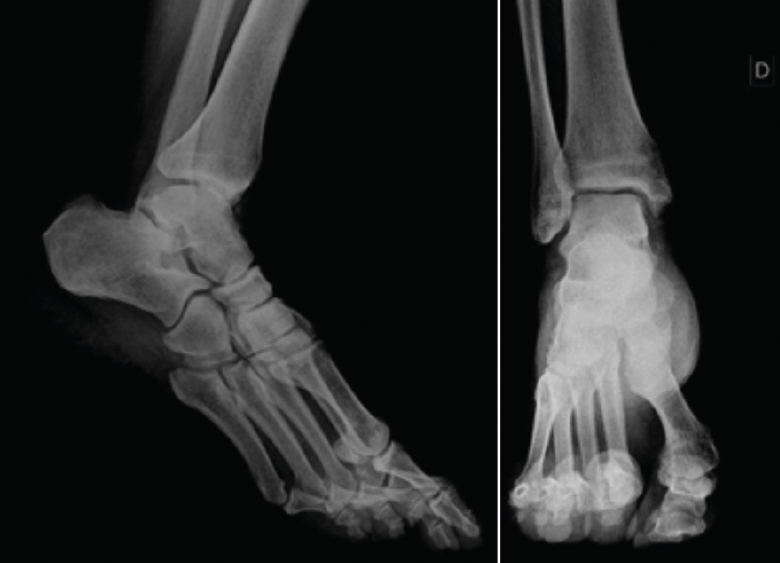

Se presenta el caso de un paciente varón de 54 años de edad, de profesión repartidor, que refiere una caída desde la plataforma de un camión, con torsión del tobillo derecho. Acude deambulando con la ayuda de un bastón. A la exploración física del tobillo derecho, presenta un balance articular disminuido con respecto al contralateral. Muestra dolor difuso a la palpación del ligamento peroneoastragalino anterior y posterior, y en la cúpula astragalina en la cara anterior del tobillo. No presenta dolor a la compresión de la sindesmosis. No da impresión de inestabilidad con maniobras de varo/valgo. En la radiografía se descartan fractura o signos indirectos de lesiones de partes blandas (Figura 1).

Figura 1. Radiografía anteroposterior y lateral del tobillo derecho.